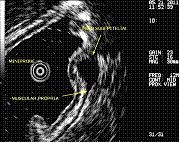

A Ecoendoscopia Digestiva, ou ultra-sonografia endoscópica (USE), é um exame que combina endoscopia e ecografia de alta resolução. O aparelho utilizado para a realização do exame designa-se ecoendoscópio. Trata-se de um endoscópio fino e flexível, especialmente equipado com uma sonda (transdutor) de ecografia em miniatura que se encontra acoplada à extremidade do aparelho, e que permite a realização de ecografia no interior do tubo digestivo.

O ecoendoscópio combina duas modalidades que, em simultâneo, integram a visão endoscópica e a ultra-sonografia de alta frequência.

O ecoendoscópio pode ser introduzido através da boca (Ecoendoscopia Digestiva Alta, para avaliação do esófago, estômago e duodeno) ou do ânus (Ecoendoscopia Digestiva Baixa, para avaliação do cólon e reto). O transdutor ecográfico permite obter imagens detalhadas das diversas camadas da parede do tubo digestivo em toda a sua espessura, bem como avaliar em profundidade outras estruturas vizinhas do aparelho digestivo, incluindo gânglios linfáticos, vasos sanguíneos e, no caso da Ecoendoscopia Digestiva Alta, o mediastino, pulmões, fígado, vesícula biliar, vias biliares e pâncreas, glândula suprarrenal, rim, ou seja, qualquer órgão ou estrutura próximo ao aparelho digestivo.

Enquanto a endoscopia clássica apenas permite observar a mucosa (camada mais interna do aparelho digestivo), a ecoendoscopia permite, através do transdutor ecográfico posicionado no interior da lúz do órgão, avaliar todas as camadas da parede do tubo digestivo e eventual patologia aí existente.